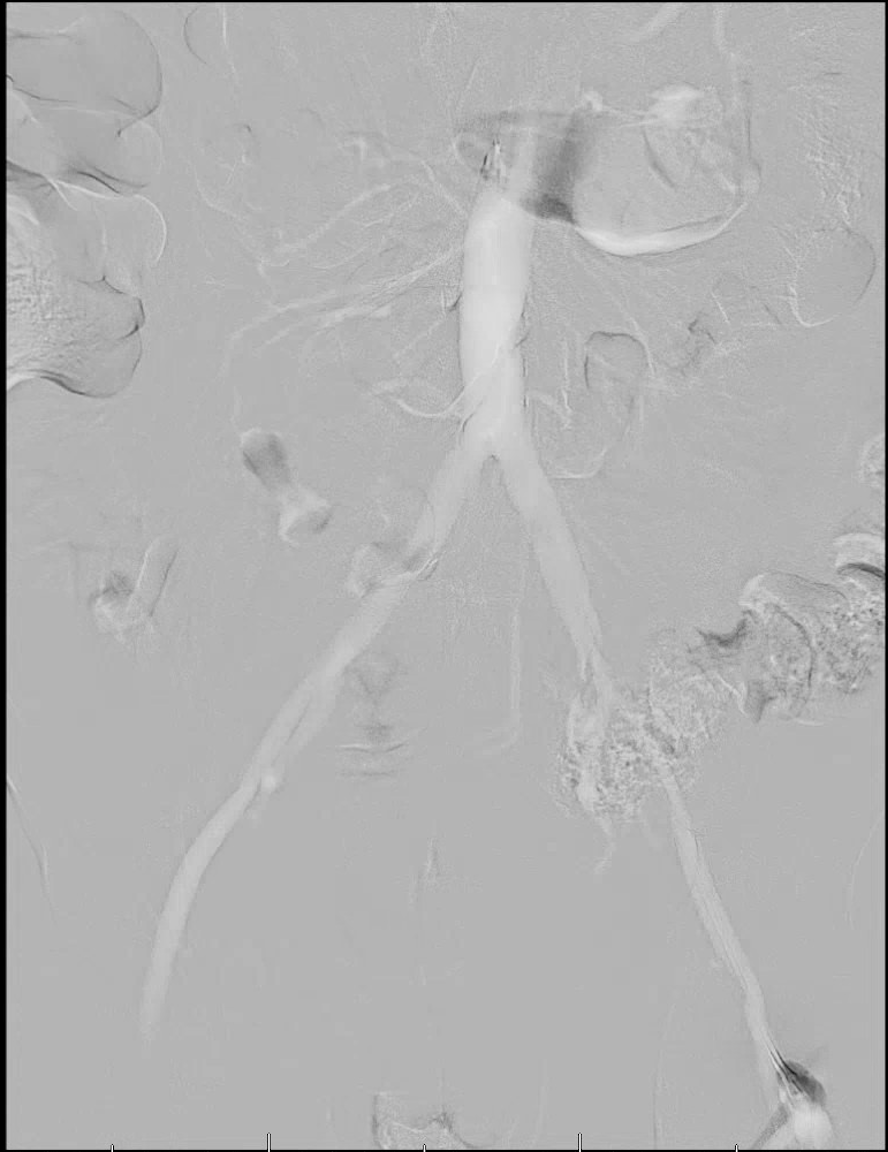

There are several unique properties of carbon dioxide that allow for its use as a contrast agent.10-12 For starters, carbon dioxide displaces the blood rather than mixing with it like an iodinated contrast. It is also less dense than surrounding bodily tissues and is therefore considered a negative contrast agent. Due to this, digital subtraction fluoroscopy is necessary to remove the surrounding anatomic structures and highlight the vascular structures while performing this technique. The vessels will appear bright on carbon dioxide angiograms whereas they appear dark using traditional methods. The gas is also buoyant, meaning it preferentially fills the anterior portion of larger blood vessels when patients are in a supine position. To improve visualization, physicians often take the feet out of the dependent position and elevate them by about 15 degrees.

Perhaps the greatest criticism of carbon dioxide angiography is poor image quality. Sometimes one cannot perform the procedure solely with carbon dioxide and must rely on supplemental contrast media, albeit at reduced volumes in comparison to a traditional angiogram. The distal extremities also present a unique challenge because the gas must travel the farthest distance from the injection site. However, improvements in digital subtraction angiography software and techniques have greatly improved visualization in recent years. When the carbon dioxide is injected, there may be incomplete filling of the vessel, making it appear as though there are “holes” in the image. By digitally stacking multiple areas of the same vessel segment, a more complete picture can emerge. If this does not occur, one may mistake the “holes” for areas of stenosis.19

In 2014, Fujihara and colleagues conducted a prospective multicenter study of 98 patients with chronic kidney disease (with an average glomerular filtration rate of 35 mL/min) who presented with lesions of the renal, aortoiliac and superficial femoral arteries.20 The average volume of carbon dioxide was 281 ± 156 mL supplemented with only 15 ± 18 mL of iodinated contrast. Five percent of patients developed contrast-induced nephrotoxicity and 10 percent of patients reported transient leg pain. The authors reported a 97.9 percent success rate with ankle brachial indices (ABIs) improving from 0.66 to 0.83 three months after superficial femoral artery intervention.20

In 2016, Stegemann and coworkers performed a retrospective review of 154 patients who had traditional angiography and 37 patients who had carbon dioxide angiography with supplemental iodinated contrast.21 There were 29 cases of contrast-induced nephrotoxicity in the traditional angiography group in comparison with two cases in the carbon dioxide group. The amount of iodinated contrast used in the traditional angiography group was 113 ± 76 mL as opposed to only 34 ± 41 mL in the carbon dioxide angiography group. There was a 96 percent success rate in the traditional angiography group and a 100 percent success rate in the carbon dioxide group. The authors concluded that carbon dioxide angiography is a viable alternative but may be most useful in situations in which image accuracy is not critical, or when supplementation with iodinated contrast would not be absolutely contraindicated.

In 2016, Palena and colleagues conducted a prospective study of 36 patients with an average age of 74.8 years who had chronic kidney disease of stage 3 or greater (glomerular filtration rate ≤60 mL/min, the accepted definition across all studies) and critical limb ischemia.22 They initially performed a traditional angiogram with iodinated contrast medium so they could attain a comparison of image quality postoperatively but the intervention occurred solely with the guidance of carbon dioxide. The transcutaneous oxygen pressure improved from 11.8 ± 6.3 to 58.4 ± 7.6 mmHg. Carbon dioxide angiography had good sensitivity (92.3 percent) but slightly lower specificity (75 percent) and negative predictive value (63.1 percent), meaning that lesions could have been missed.22